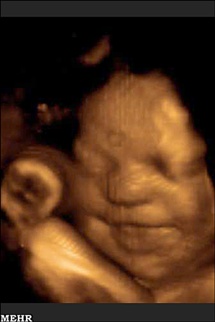

جنین پیش از تولد حرکت دادن اجزای صورت خود را آغاز می کند، بینی اش را چین می اندازد و یا ابروهایش را بالا می برد، حرکاتی که دانشمندان به تازگی دریافته اند با رشد روز به روز جنین پیچیده تر می شوند.

به گزارش خبرگزاری مهر، با اینکه دانشمندان از گذشته نیز می دانستند که جنین ها در دوران جنینی از بیان چهره برخوردارند و می توانند اندامهای چهره خود را حرکت دهند، مطالعه جدید، این حرکات بر روی چهره جنین ها را در طول زمان مورد بررسی قرار داده است.

به گفته محققان دانشگاه دارهام در انگلستان آنچه به تازگی کشف شده این است که پیچیدگی حرکات صورت جنین ها در طول زمان تا پیش از متولد شدن روز به روز افزایش پیدا می کند. محققان برای بررسی این روند از دو جنین از سن 24 تا 35 هفتگی تصویربرداری کرده و پیشرفت حرکات صورت آنها را تا زمانی که به ترکیبی از حرکات پیچیده مرتبط با بیانات قابل تشخیص چهره تبدیل شدند را مورد بررسی قرار دادند.

در پی ردیابی 19 حرکت در صورت جنین ها محققان بر روی حرکاتی متمرکز شدند که با بیان دو حالت، گریه کردن و خندیدن در ارتباط بودند. در طول زمان حرکات مرتبط با این دو حالت ترکیبهای پیچیده تری پیدا کردند.محققان برای تصویربرداری از جنین ها از سیستم تصویربرداری فراصوت چهار بعدی استفاده کردند تا بتوانند حرکات مرتبط با بیان چهره را در دو جنین دختر مورد بررسی قرار دهند. در سن 24 هفتگی جنینها حرکتهای ساده ای مانند بازکردن لبها را انجام می دادند. با گذشت چند هفته جنینها ترکیب حرکات را آغاز کردند و هنگام بازکردن لبها، بینی خود را نیز چین می دادند. در هفته سی و پنجم ترکیبی از سه یا چهار حرکت مرتبط با دو بیان چهره (گریه و خنده) در جنینها مشاهده شد.محققان می گویند این حرکات در چهره جنین ها به این معنی نیست که احساس خاصی به جنین ها دست داده است، زیرا جنین ها هنوز از قدرت کافی برای داشتن احساسات برخوردار نیستند. به علاوه به نظر می آید این حرکات نوعی آماده سازی جنین برای ورود به جهانی اجتماعی باشد، جایی که باید با دیگران ارتباط برقرار کنند. جنین ها همچنین انگشت شست خود را به دهان برده و می مکند و حرکاتی مبنی بر تنفس کردن از خود نشان می دهند که هر دوی این حرکات زمینه ساز رفتارهایی هستند که پس از متولد شدن برای ادامه بقای آنها حیاتی به شمار می روند.بر اساس گزارش لایو ساینس، محققان قصد دارند در آینده بر روی حرکات صورت جنین ها که با حالتهای عصبانیت، خنده و غمگینی در ارتباط هستند متمرکز شوند.